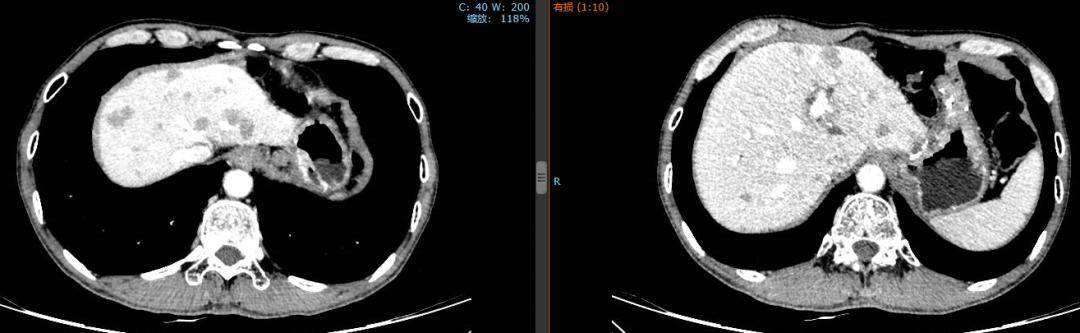

2018年10月23日至2019年2月3日行顺铂+氟尿嘧啶联合赫赛汀方案治疗5周期,疗效评估PR。

2019年1月24日,经4个周期赫赛汀+DF后,患者肝脏转移灶明显缩小。

2018年10月17日,化疗前

2019年1月24日,化疗后

患者化疗后出现3度胃肠道反应,3度骨髓抑制。第5周期化疗后出现感染性休克,遂停止联合化疗。